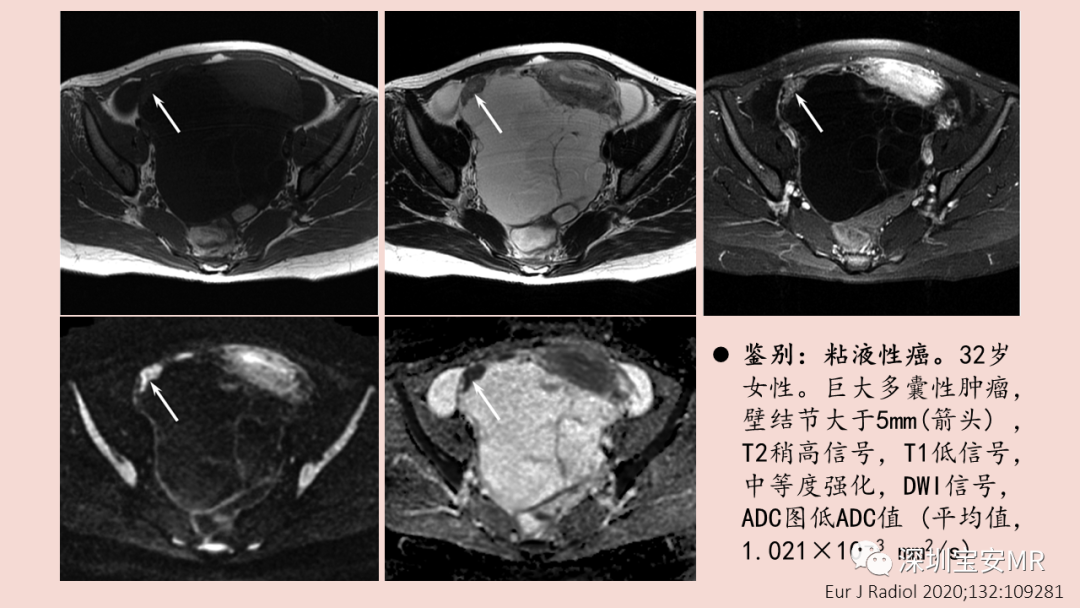

图片